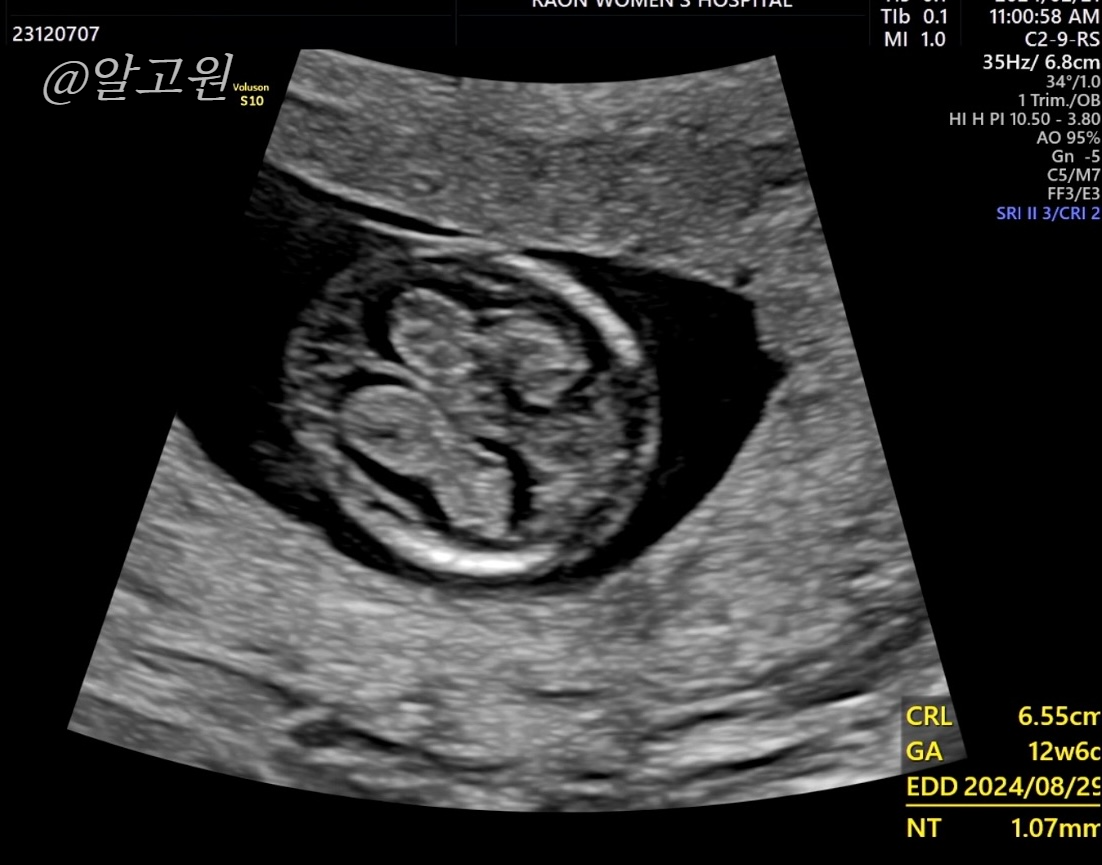

초음파로 목투명대, 척추와 뼈, 장기, 뇌 모양, 심장박동소리, 태반 위치 등

선생님께서 아주 꼼꼼히 봐주십니다.

다행히도 유동이는 정상,정상,정상!

목투명대도 1mm로 정상수치에 들었어요.

(3mm 이하면 정상, 이상일 경우 추가 검사진행)